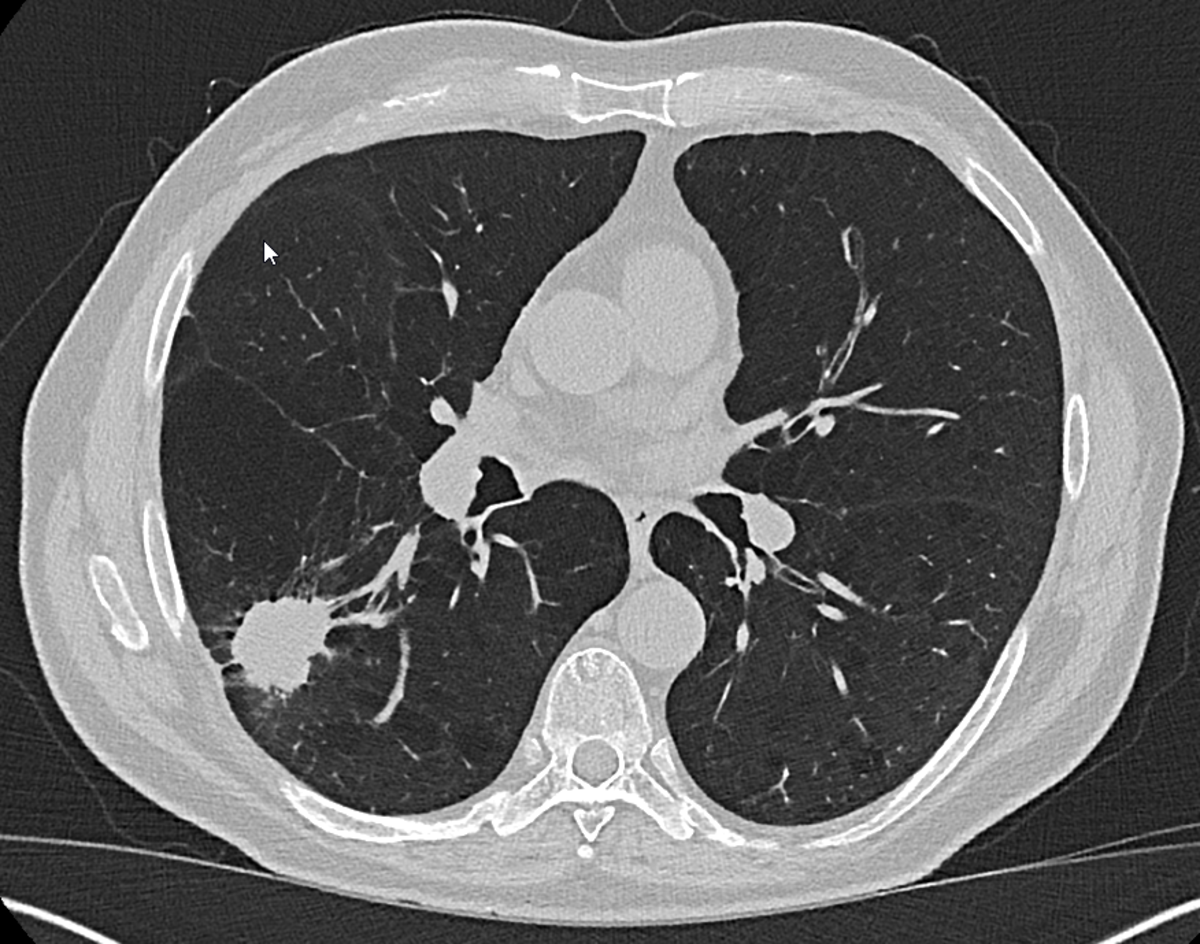

Eine weitere Neuheit im Rahmen der neuen Lungenkrebsvorsorge: Erstmals ist auch die Nutzung einer Software zur automatischen Lungenrundherderkennung verpflichtend, die im Anschluss an die Befundung sowohl vom Erst- als auch Zweitbefunder genutzt werden muss. (Bild © UKA)

Typische Tumornarbe. Die Entfernung erfolgt in der Regel in einer Operation mit minimalinvasiven Verfahren („Schlüssellochtechnik“) (Bild © UKA)